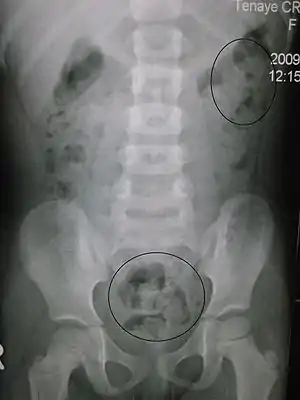

| Constipation in a young child seen on X-ray. Circles represent areas of fecal matter (stool is white surrounded by black bowel gas). | |